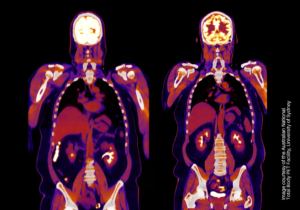

TB-PET can be used to capture molecular processes from all organs simultaneously. The high-performance instrument can be used to study diseases that affect the entire body and build a better picture of complex processes such as ageing, metabolism, brain signalling and drug interactions.

Due to its exquisite sensitivity, it also has the potential to use much lower radiation doses compared to conventional PET scanners, making it safe to scan children, healthy volunteers, and to scan patients repeatedly to better understand disease progression and treatment effects.

Dr Tao Sun from the Shenzhen Institute of Advanced Technology, Chinese Academy of Sciences presents a recently proposed framework that applies network analysis principles on Total Body PET data to identify metabolic dysfunctions at the system level.

Overview of the technical specifications and capabilities of the new Biograph Vision Quadra Total Body PET system set to be installed.